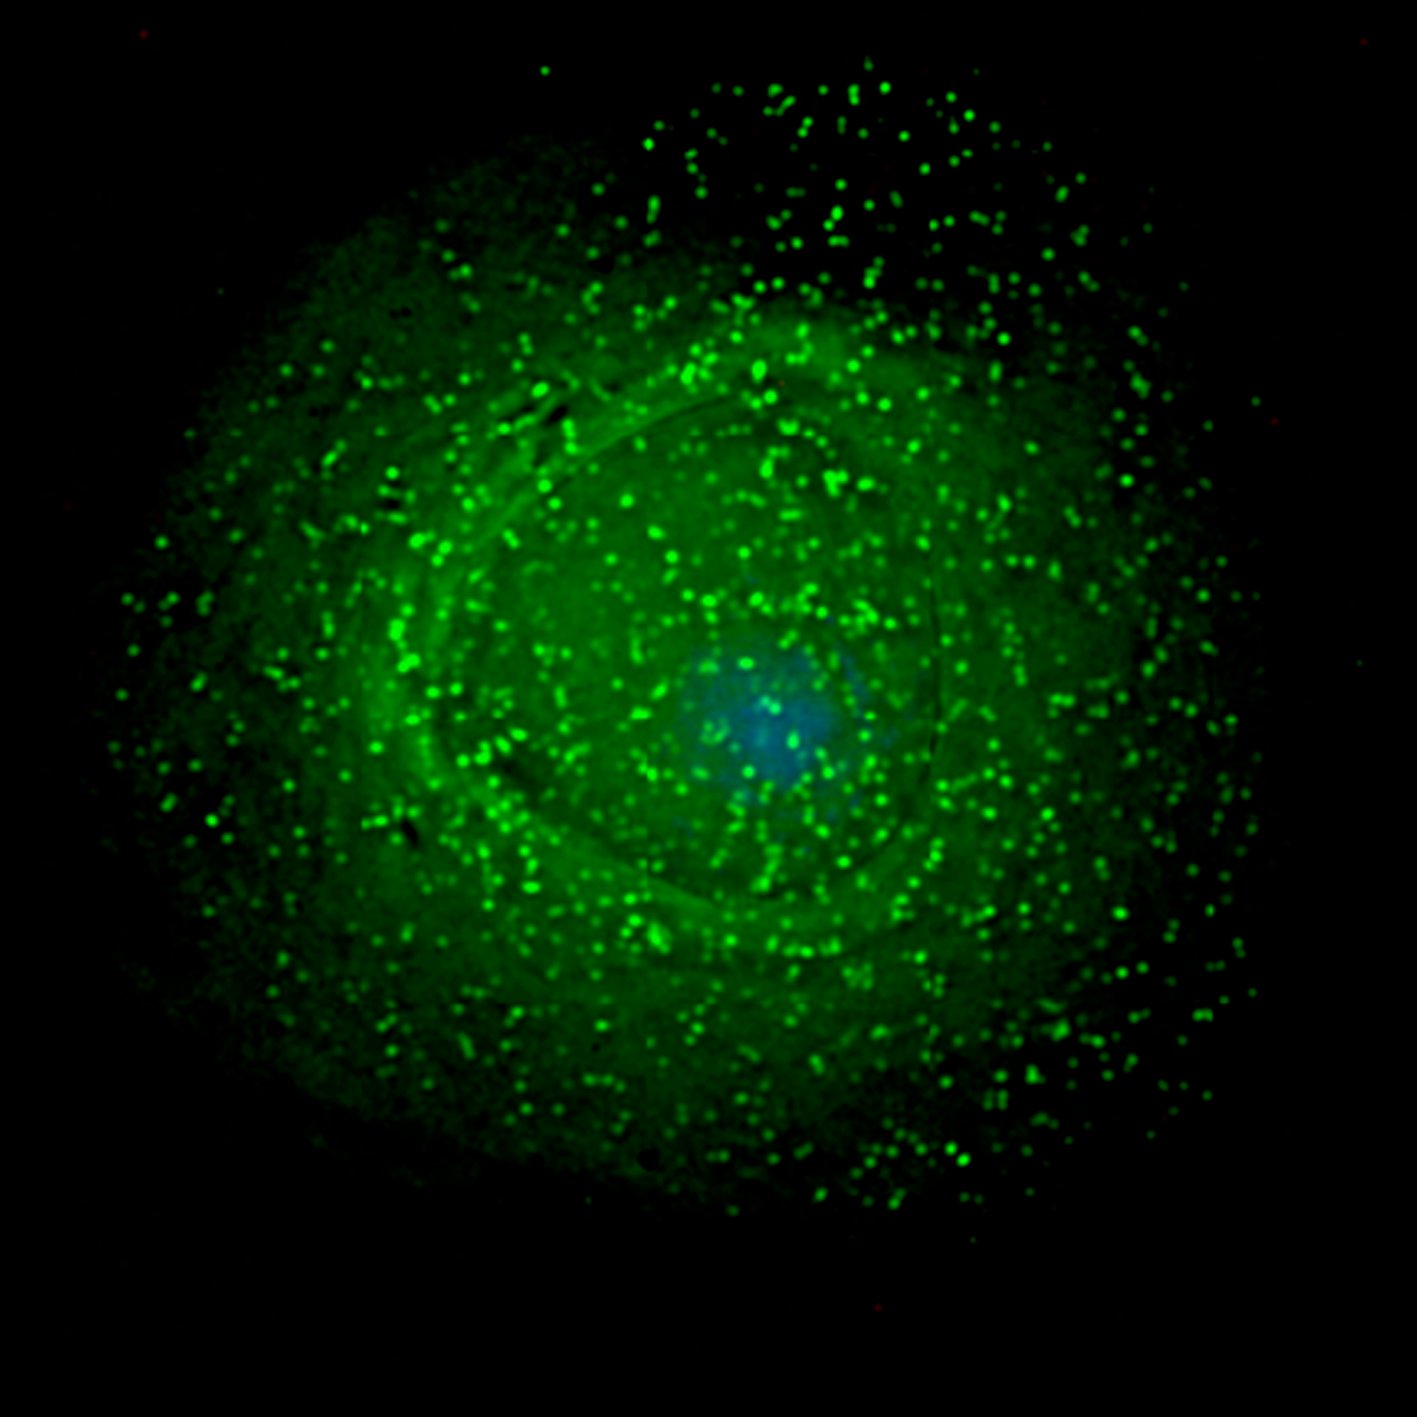

HIV-1 tends to move quickly through the body. So quickly, in fact, that it doesn’t give the body enough time to react to or even detect its presence. The virus reaches the immune cell’s nucleus by way of microtubules and attaches itself to bicaudal D2, which calls upon a molecular motor called a dynein to move along the microtubules. You could say that HIV-1 uses bicaudal D2 as a boarding pass for the biological train that will take it nonstop to its final destination within the cell: the nucleus.

That being said, if HIV-1 doesn’t have that protein, it essentially becomes stranded.

“By preventing its normal movement, we essentially turned HIV-1 into a sitting duck for cellular sensors,” explained Edward M. Campbell, Ph.D., corresponding author of the study and associate professor in the Department of Microbiology and Immunology of Loyola University Chicago Stritch School of Medicine.

The study carried out by Campbell and his team opens up the possibility of creating a drug that can prevent HIV-1 from binding to bicaudal D2. As explained by Medical Express, the introduction of such a drug would leave HIV-1 stranded in the cytoplasm — an area within the immune cell that’s thick with proteins and mitochondria. The virus must navigate through the cytoplasm to reach the nucleus, but it’s not an easy journey.